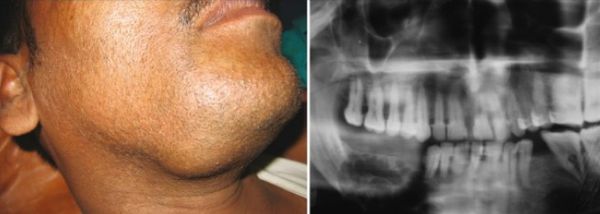

Клинический случай №5

Пациент муж., 17 лет. КТ-исследование подтверждает наличие новообразований (Рис. 6,7).

Рис. 6. Ортопантомограмма пациента с одонтогенными кератокистами.

КТ свидетельствует о наличии множественных одонтогенных кератокист. Определяются множественные овальные, зубосодержащие полости, с четкими ровными справа и полицикличными контурами слева, однородной рентгенпрозрачности. В теле и ветвях нижней челюсти образование распространяется вдоль кости от премоляров справа и моляров слева и до вершин мыщелковых отростков. Костные структуры незначительно увеличены в размерах за счет вздутия, кортикальные пластины истончены. Дивергенция корней зубов № 43, 44. Объемные зубосодержащие образования верхней челюсти вросли в верхнечелюстные синусы, занимая практически весь объем, а справа — распространилось в подвисочную ямку.